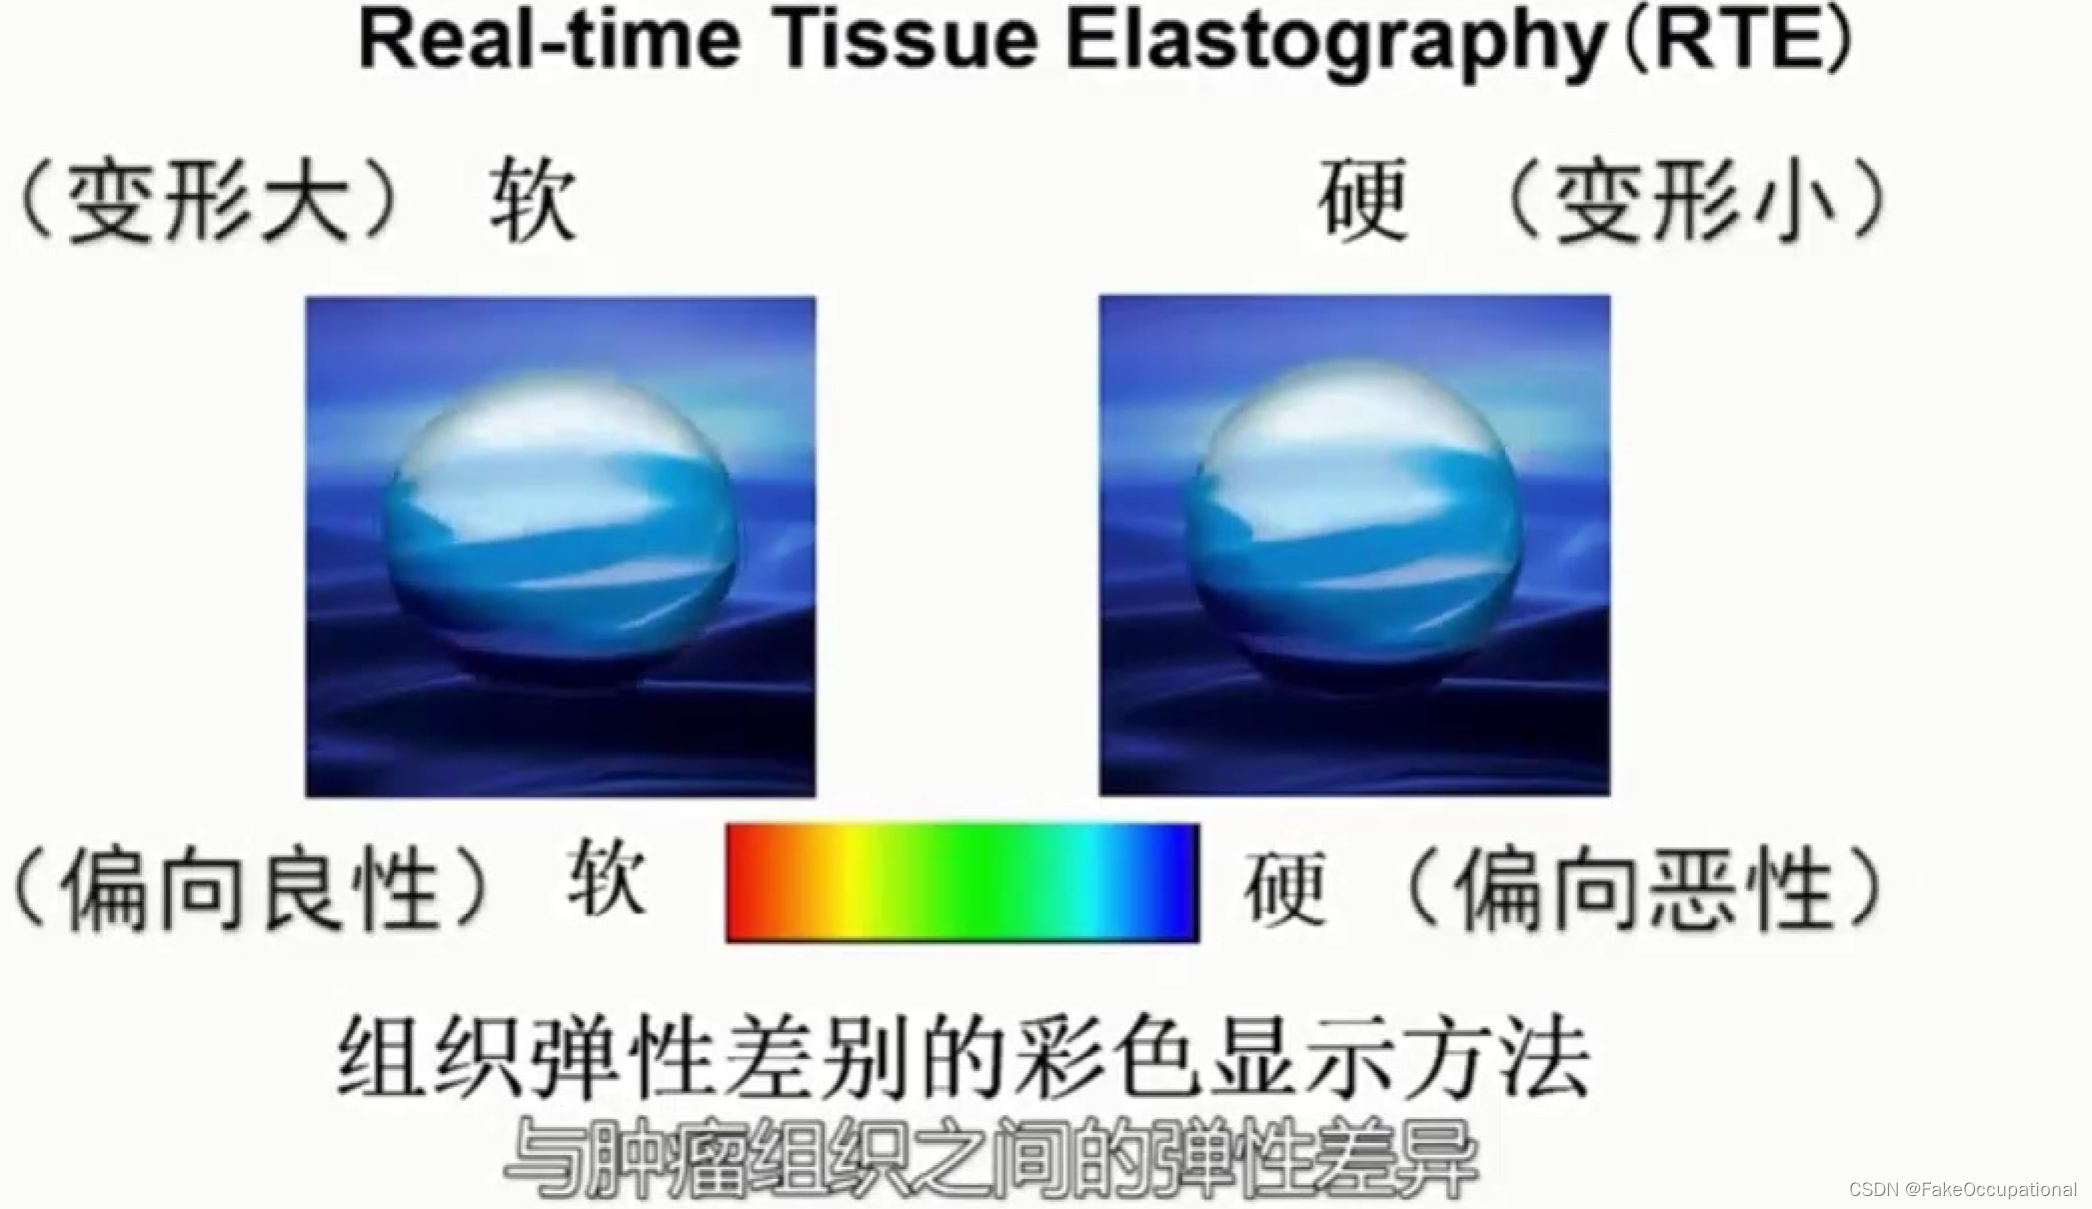

超声特殊检查与新技术

超声新技术

3.弹性成像

乳腺超声进展

- 前者以彩色编码不同组织的弹性大小,